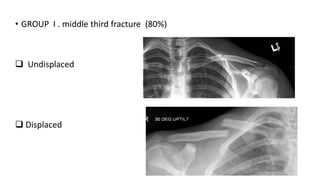

• GROUP I . middle third fracture (80%)

 Undisplaced

 Displaced

• GROUP I. middle third fracture (80%)  Undisplaced  Displaced